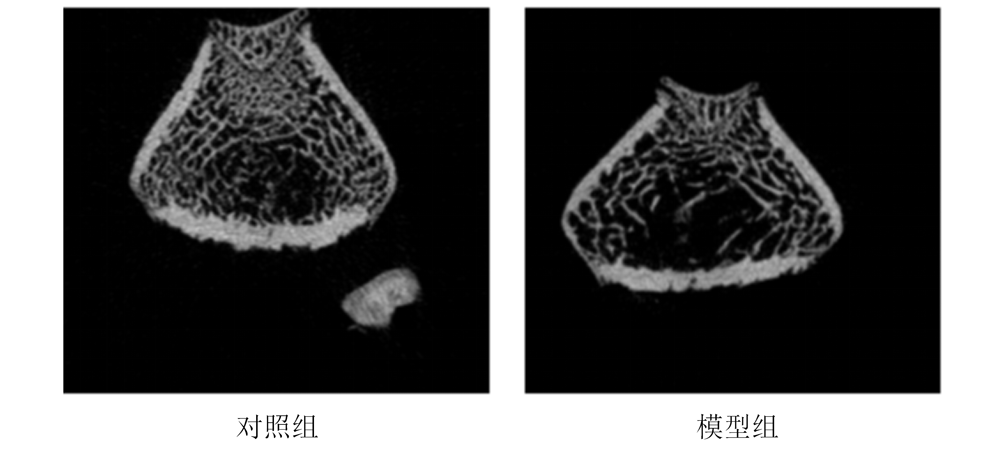

股骨Micro- CT

股骨内踝HE染色